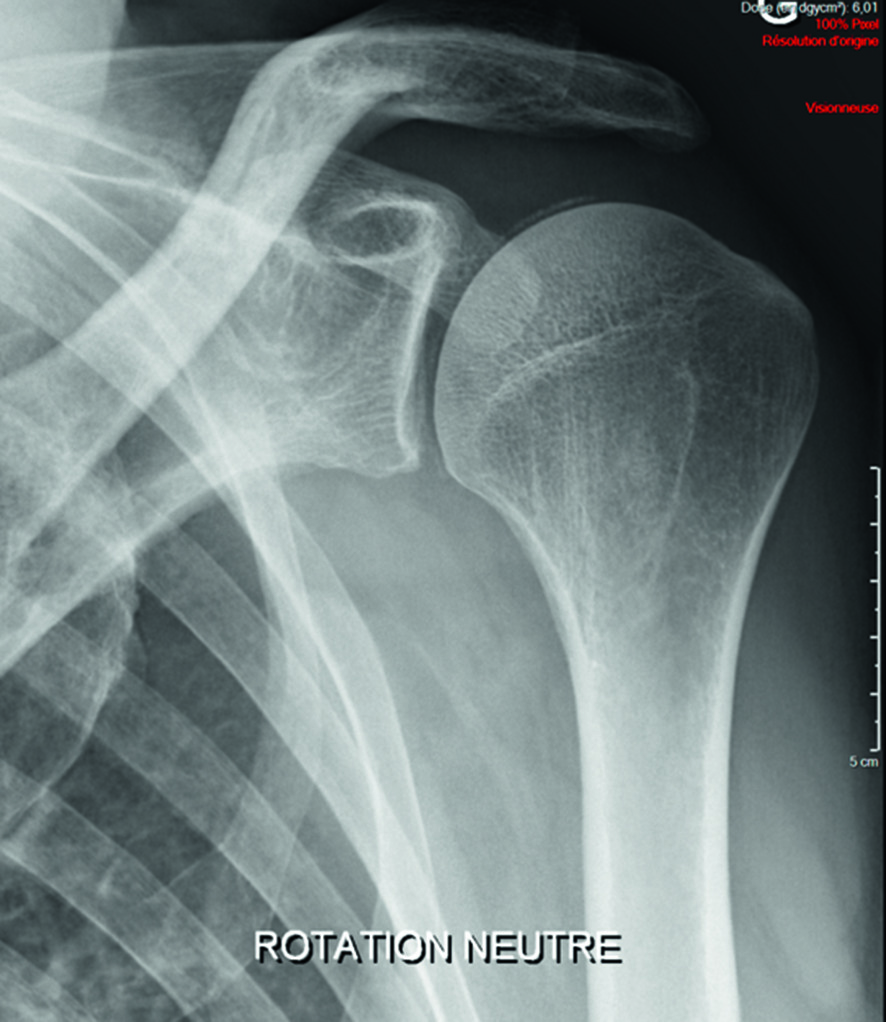

On note des signes radiographiques d’arthrose associant pincement articulaire, condensation, ostéophytose qui peuvent cependant être tardifs (fig. 30.6) (cf. aussi item 129 au chapitre 8).

Fig. 30.6. :

Aspect d’omarthrose excentrée associant pincement articulaire localisé, condensation, ostéophytose de la partie inférieure de la tête humérale, disparition de l’espace sous-acromial.

L’omarthrose primitive dite centrée dans le plan frontal est plus rare et correspond à une véritable atteinte arthrosique de l’articulation glénohumérale avec pincement de l’interligne, condensation sous-chondrale et ostéophytose le plus souvent polaire inférieure avec notamment ostéophyte huméral inférieur en « barbichette » ; elle peut être primitive ou survenir après des lésions cartilagineuses glénohumérales secondaires à une atteinte inflammatoire (polyarthrite rhumatoïde), infectieuse (arthrite septique) ou microcristalline (chondrocalcinose).